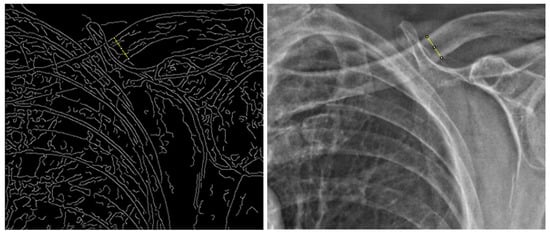

2.2. Graphical Analysis